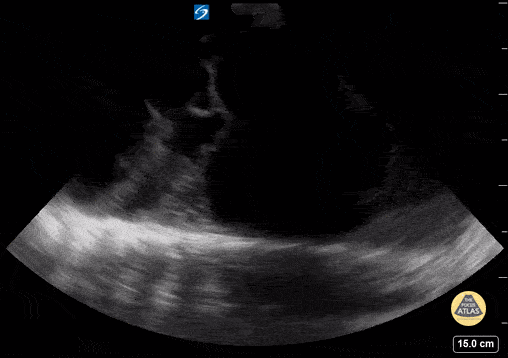

Peds-Lung - Loculated Pleural Effusion

16 yo with initial diagnosis of pneumonia. Worsening shortness of breath. Found to have a loculated pleural effusion on POCUS. Contributor: Kathryn Pade, MD, Rady Children's Hospital San Diego